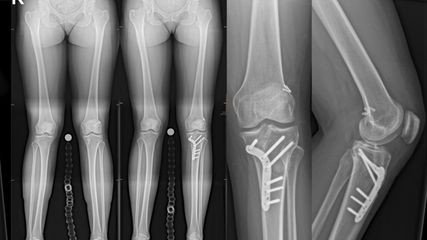

Aktuell müssen bezüglich Extremitätenerhalt somit individuelle Entscheidungen, auch unabhängig der gängigen Scores, getroffen werden, wie etwa in dem Fall einer 68-jährige Patientin, die als Fahrradfahrerin von einem PKW erfasst wurde. Sie erlitt dabei eine drittgradig offene Unterschenkelfraktur linksseitig (Abb.1a) mit ausgedehntem Knochendefekt (20cm tibial und 10cm fibular) inklusive komplettem Verlust der Sprunggelenksgabel (Abb. 1b) sowie einer Rissquetschwunde im Bereich der Kniekehle mit Décollement nach distal. Zusätzlich zog sie sich eine zweitgradig offene Querfraktur des Humerusschaftes rechts mit primärer Radialisläsion, eine Femurschaftfraktur rechts, eine Bimalleolarfraktur rechts und ein Schädelhirntrauma I. Grades zu (Injury Severity Score 26). Obwohl im Sinne der gängigen Scores nicht allseits die Amputationsgrenze erreicht wurde (kontra Amputation: LSI 5 Punkte, NISSA 9 Punkte, PSI: 7; pro Amputation: MESS 7 Punkte), erfolgte aufgrund des ausgedehnten Knochendefektes die primäre Kniegelenksexartikulation.

Abb. 1: 68-jährige Patientin: drittgradig offene Unterschenkelfraktur linksseitig (a) mit ausgedehntem Knochendefekt inklusive komplettem Verlust der Sprunggelenksgabel (b) sowie Rissquetschwunde im Bereich der Kniekehle mit Décollement nach distal. Zusätzlich zweitgradig offene Querfraktur des Humerusschaftes rechts mit primärer Radialisläsion, Femurschaftfraktur rechts, Bimalleolarfraktur rechts und SHT I. Grades. Obwohl im Sinne der gängigen Scores nicht allseits die Amputationsgrenze erreicht wurde, erfolgte aufgrund des ausgedehnten Knochendefektes die primäre Kniegelenksexartikulation